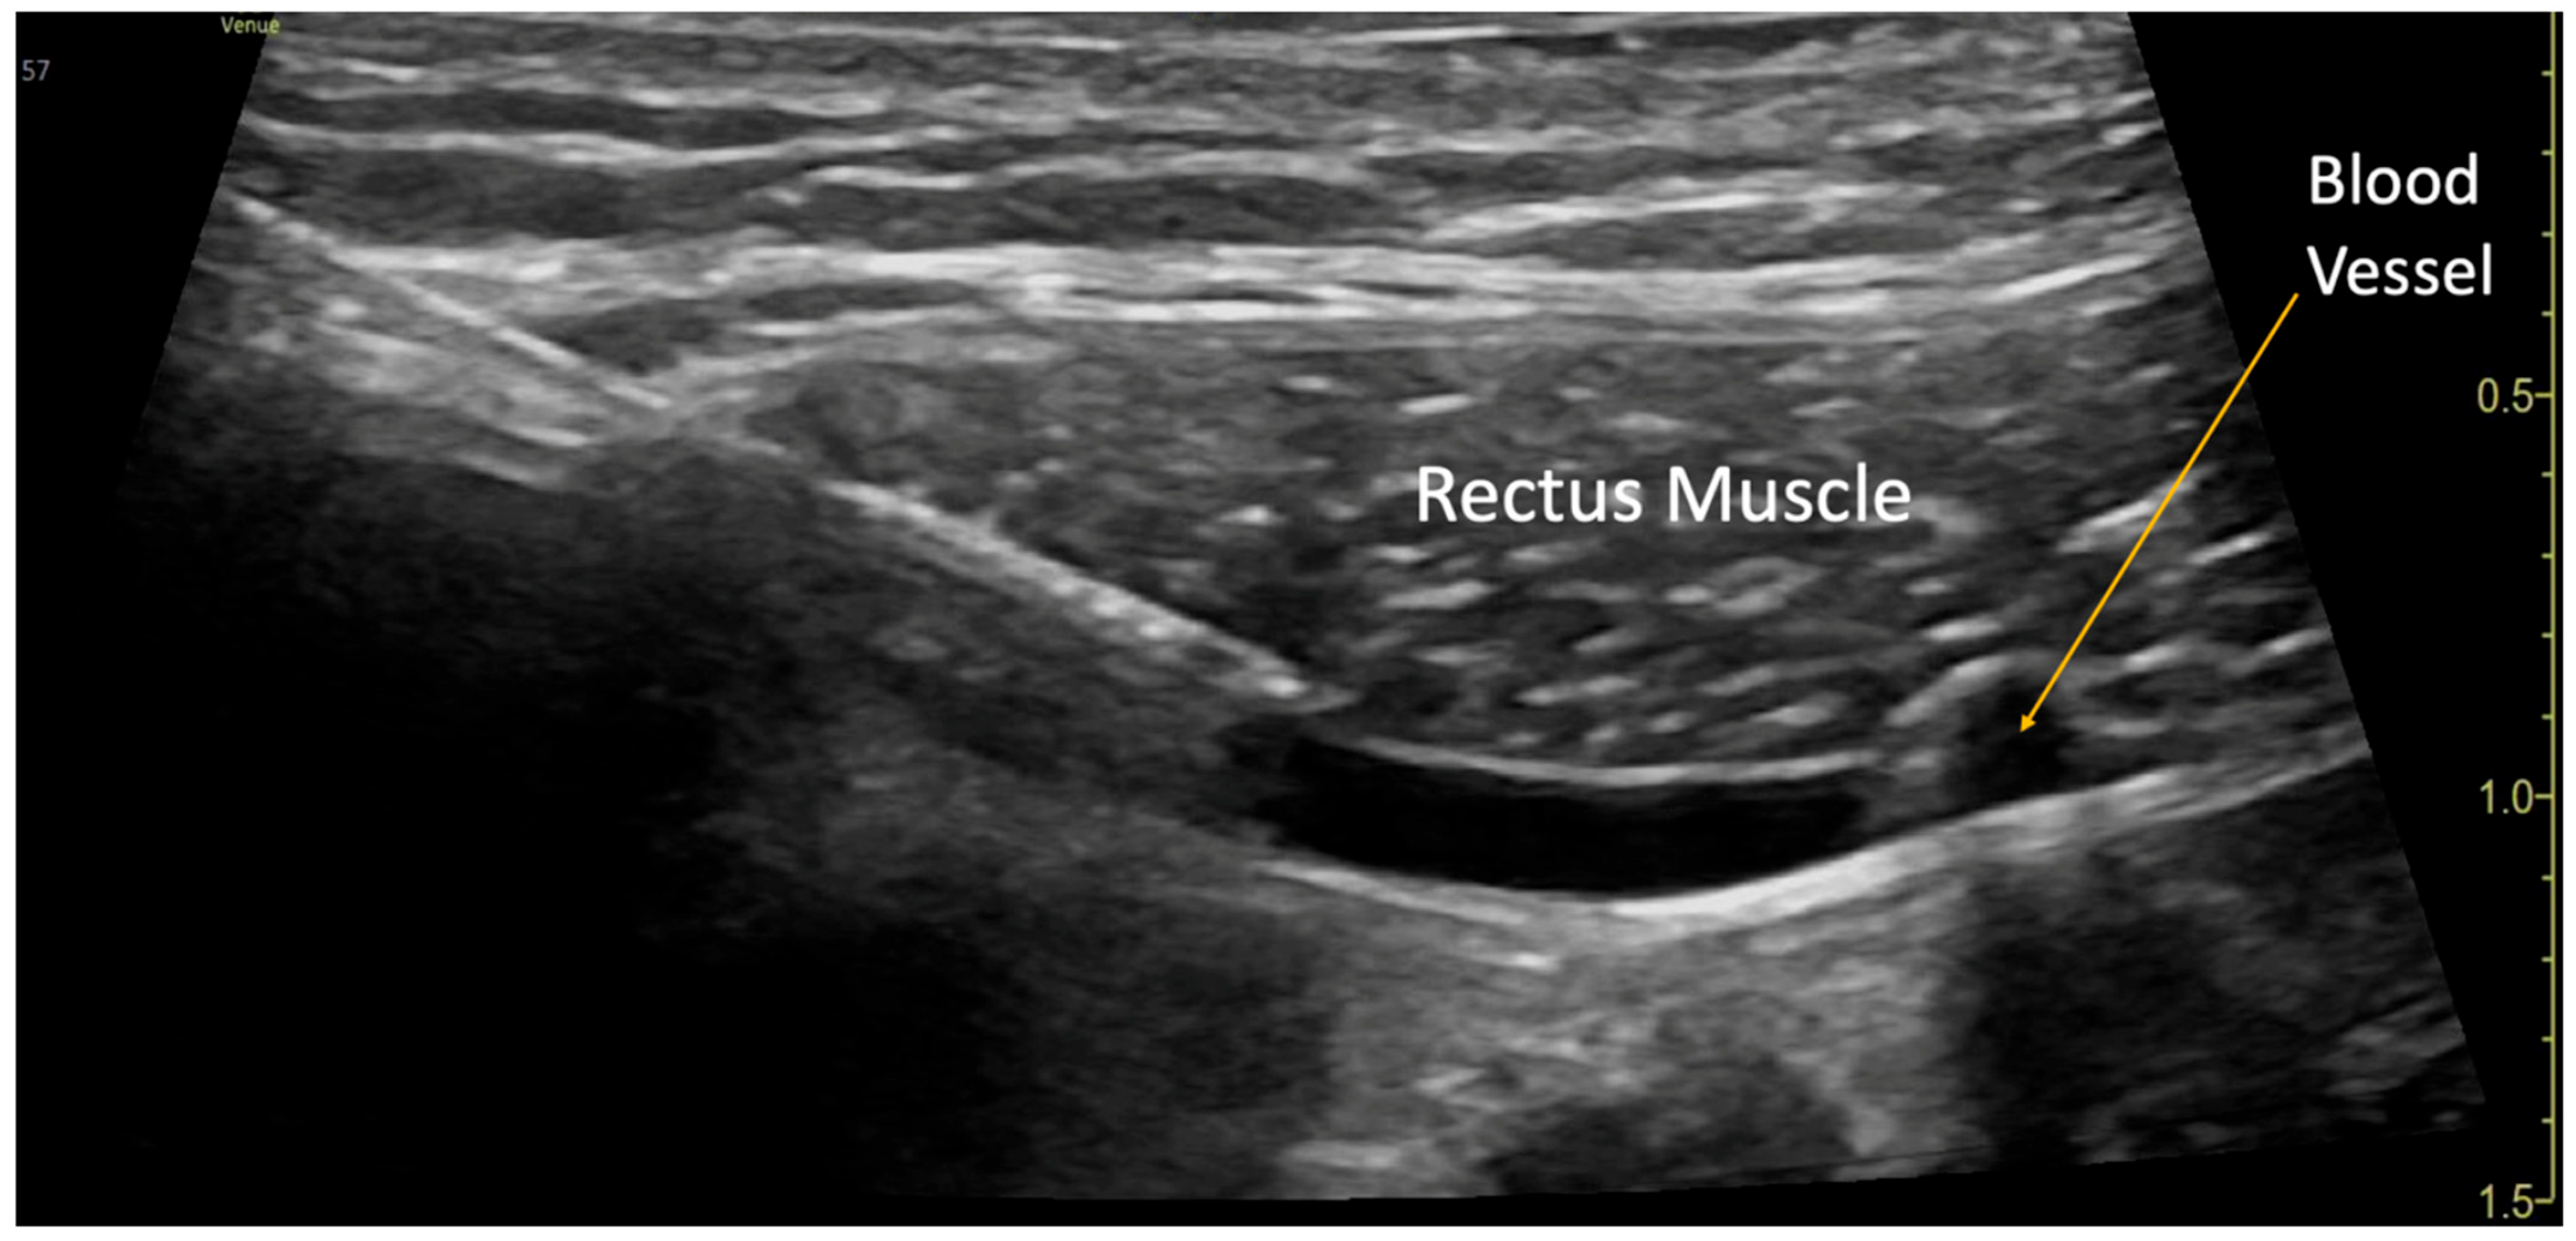

Figure 1.

Rectus Sheath Block Procedure. A blood vessel was visualized in the plane underneath the rectus muscle.

The blocks were performed while the patient was under general anesthesia, before surgery started, and after sterile preparation. A high-frequency linear transducer was positioned at the level of the umbilicus and moved laterally a few centimeters until the lateral border of the rectus muscle was visualized. An echogenic needle, 22-gauge, 50 mm Sono-TAP (Pajunck Medical Inc., Geisingen, Germany) was advanced medially from the lateral edge of the probe; final needle placement was at the lateral border of the rectus muscle, deep to the muscle, yet superficial to the posterior aspect of the rectus sheath, and not pre-peritoneal nor intraabdominal. A few milliliters (mL) of saline solution were injected until the spread of medication was visualized in the correct location (Figure 1), followed by three milliliters (mL) of local anesthetic mixture (liposomal bupivacaine 113.05 mg, bupivacaine 0.25%, 32.5 mg, and dexamethasone PF, 5 mg-total volume 22 mL). This procedure was repeated at the contralateral site. Two more bilateral local anesthetic injections under the rectus muscle were performed at the level of T7 and T12 dermatomes (Figure 2a). A total of six rectus sheath blocks were performed with 22 mL of local anesthetic mixture. After the blocks were performed, medication spread behind the rectus muscle was visualized as a bulge into the space under the rectus sheath muscle from the xiphoid to the pubic symphysis (Figure 3), as described by Visoiu et al. [14], matching the incision performed (Figure 2b) Video S1. The surgery then conducted was an open infrarenal abdominal aortic aneurysm repair with a Hemashift Gold 12 mm graft and a 6 mm limb used for aortic graft to common iliac aneurysm repair. The duration of anesthesia was 374 min, the aortic cross-clamp time was 95 min, and total blood loss for the operation was 500 mL with 180 mL of blood salvage. He also received 4500 units of Heparin during the surgery, which was reversed with 10 mg of protamine. The surgery was uneventful, and intraoperative hemodynamic stability was adequately maintained. The patient was extubated in the operating room.